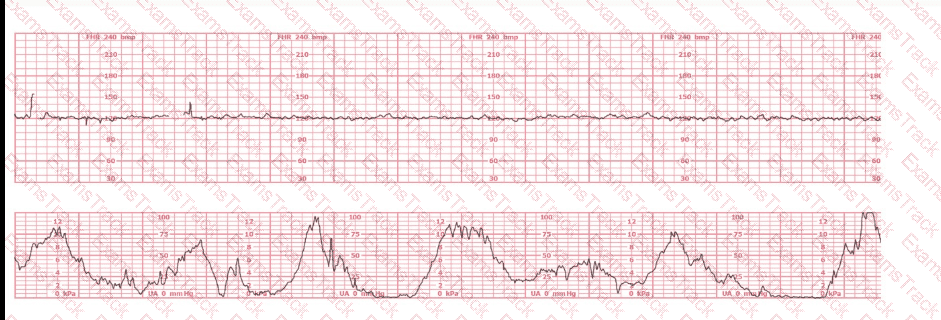

The tracing shown is a:

EFM Question 9

Options:

A.

Category I

B.

Category II

C.

Category III